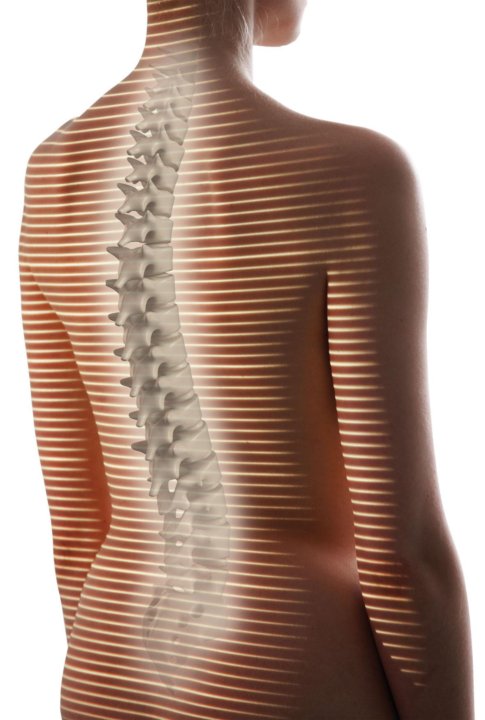

Оптическая диагностика позвоночника Diers: изображения и технологии